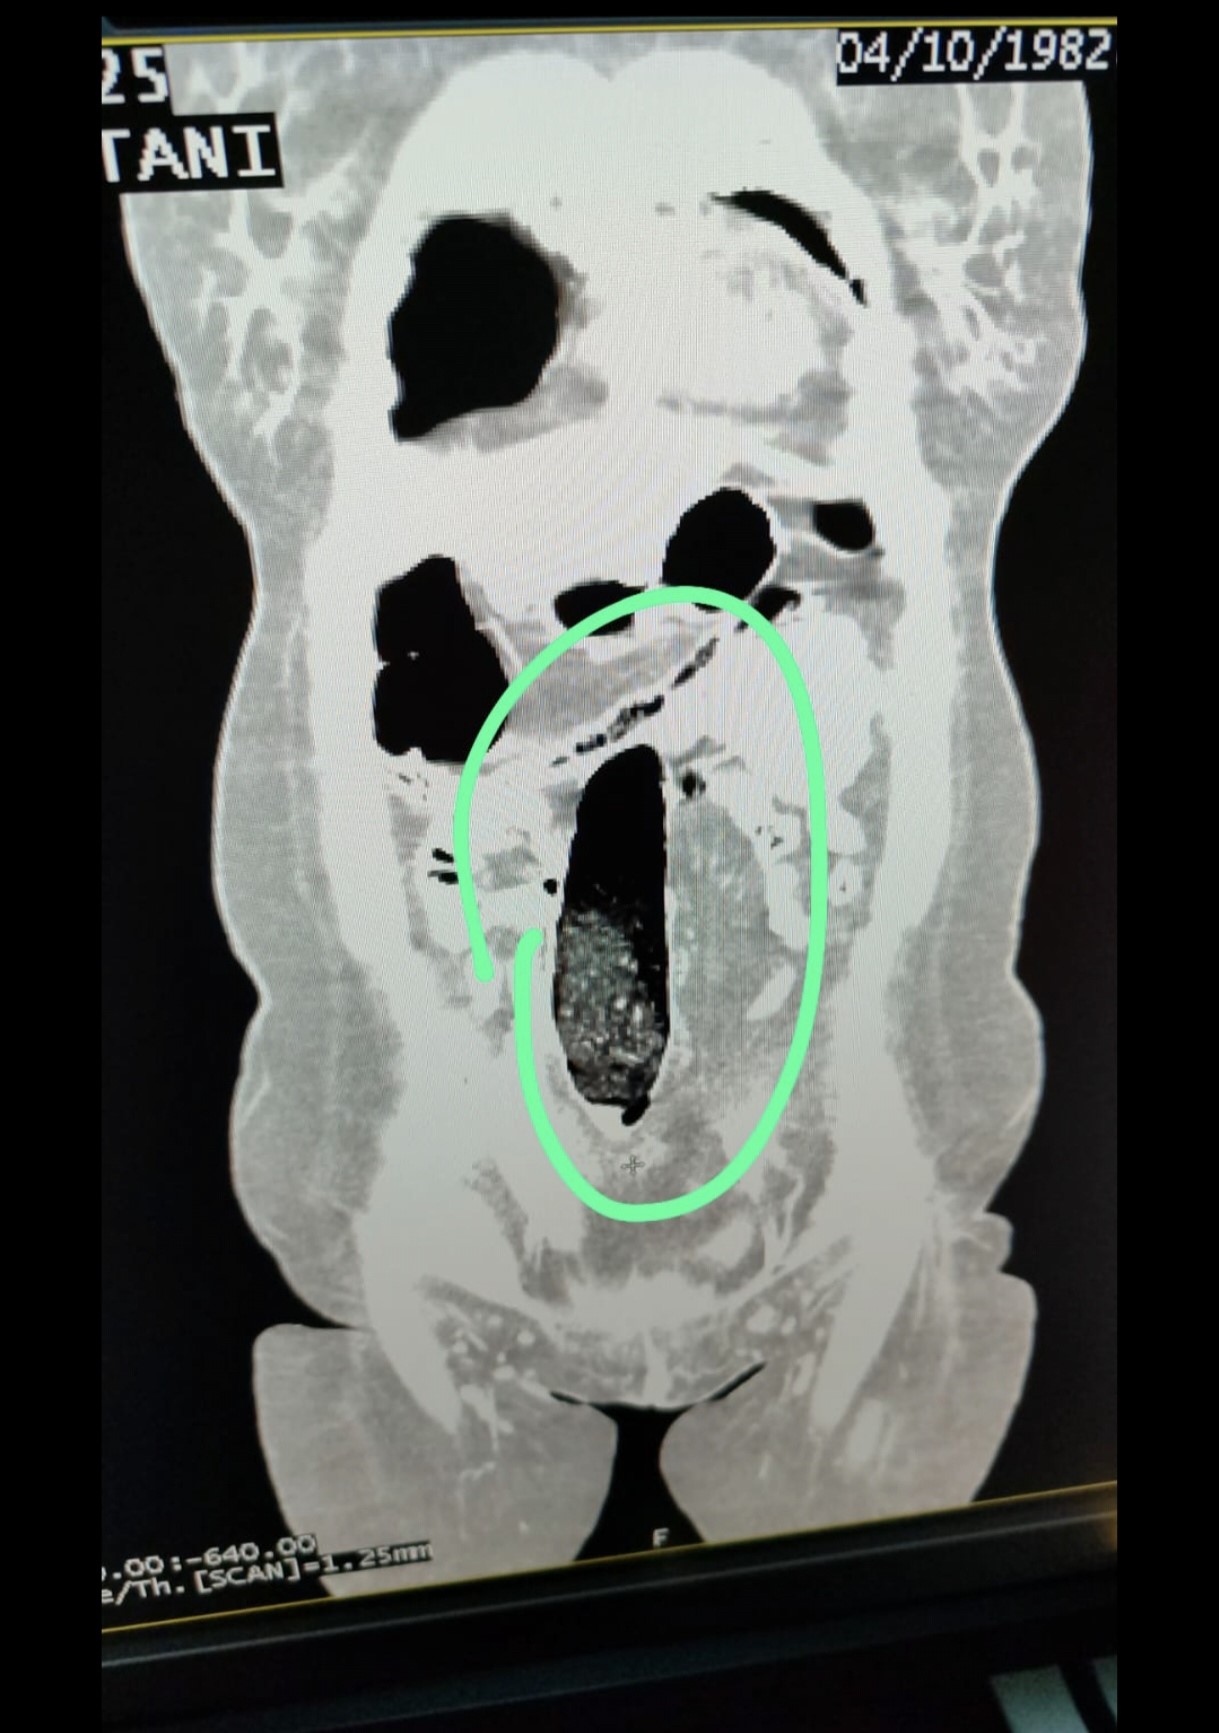

Bu kapsamda durdurulan şehirler arası yolcu otobüsünde bulunan İran uyruklu 2 şahıs üzerinde yapılan kontrollerde şüpheli durum tespit edildi. Şahısların iç beden muayeneleri sonucunda, vücutlarının doğal boşluklarında ve bağırsaklarında uyuşturucu madde bulunduğu belirlendi.

Tıbbi müdahale sonucu, F.V. isimli kadın şahıstan 3 parça halinde toplam 397,78 gram metamfetamin, S.İ. isimli erkek şahıstan ise 24 adet sentetik hap ile 3 parça halinde toplam 167,68 gram metamfetamin ele geçirildi.